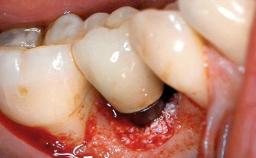

Peri-implant Carcinoma

Oral implants are highly successful and offer long-term benefits, especially in the rehabilitation of edentulous patients or patients with oral defects following ablative tumor surgery (Albrektsson and coworkers 1986), and also after radiation therapy (Schiegnitz and coworkers 2014). With the number of implants placed globally going into the millions, implant dentists have observed some rare adverse events. Although carcinogenesis around implants is an exceedingly rare phenomenon, we recently reported about 15 patients treated for carcinomas adjacent to implants at our clinical department over a period of fifteen years (Moergel and coworkers 2014). The following case represents a patient of this cohort; it discusses possible risk factors and makes suggestions for a recall schedule. A 70-year-old woman was referred to our outpatient department for evaluation of a rapidly growing macroscopic alteration of the mucosa in the left mandible.